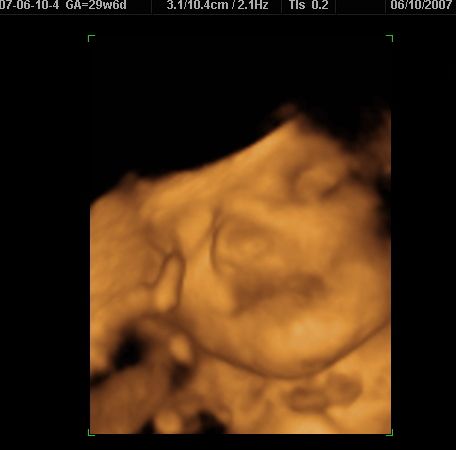

3d/4d sono yesterday w/pics...

I had it done at Impact. The baby wasnt really in the best position, so it was hard to get good shots of him, but it was still a great experience...

Image Attachment(s):